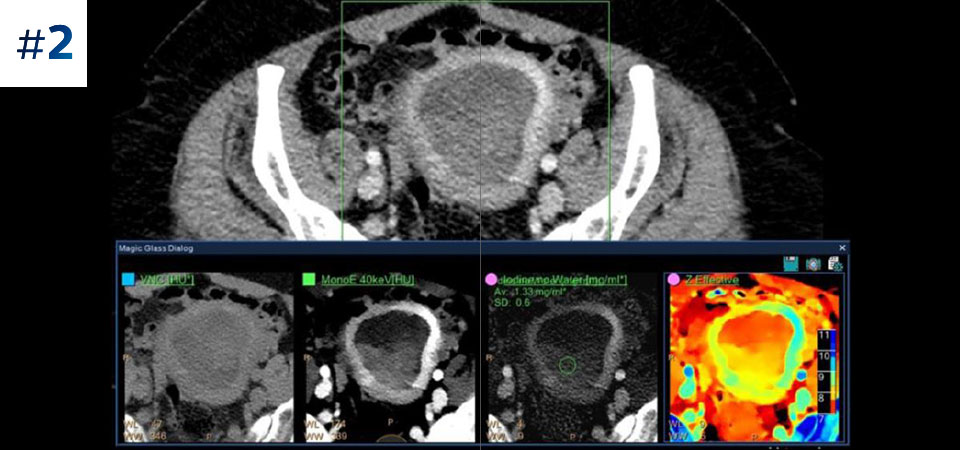

Pediatric abdomen

Go beyond conventional CT. See how layers of spectral-detector results can enhance your diagnostic confidence.